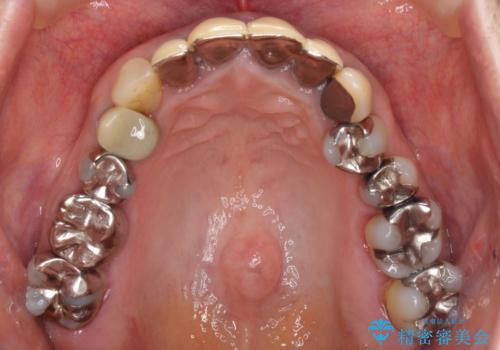

- 保険診療で装着した前歯のクラウンの変色を気にして来院された患者様です。

保険診療では樹脂を用いた素材で製作するため、水分が吸収されやすく、一緒に色素が取り込まれるために変色をしてしまいます。

また、裏打ちに主に銀を用いた金属材料を使用するため、金属自体が黒くなったり、イオンとなり溶け出したりして、歯肉ラインが黒くなってしまうことがあります。

金属の土台を歯の色に近いものへと変更した上で、オールセラミッククラウンにて補綴することとしました。